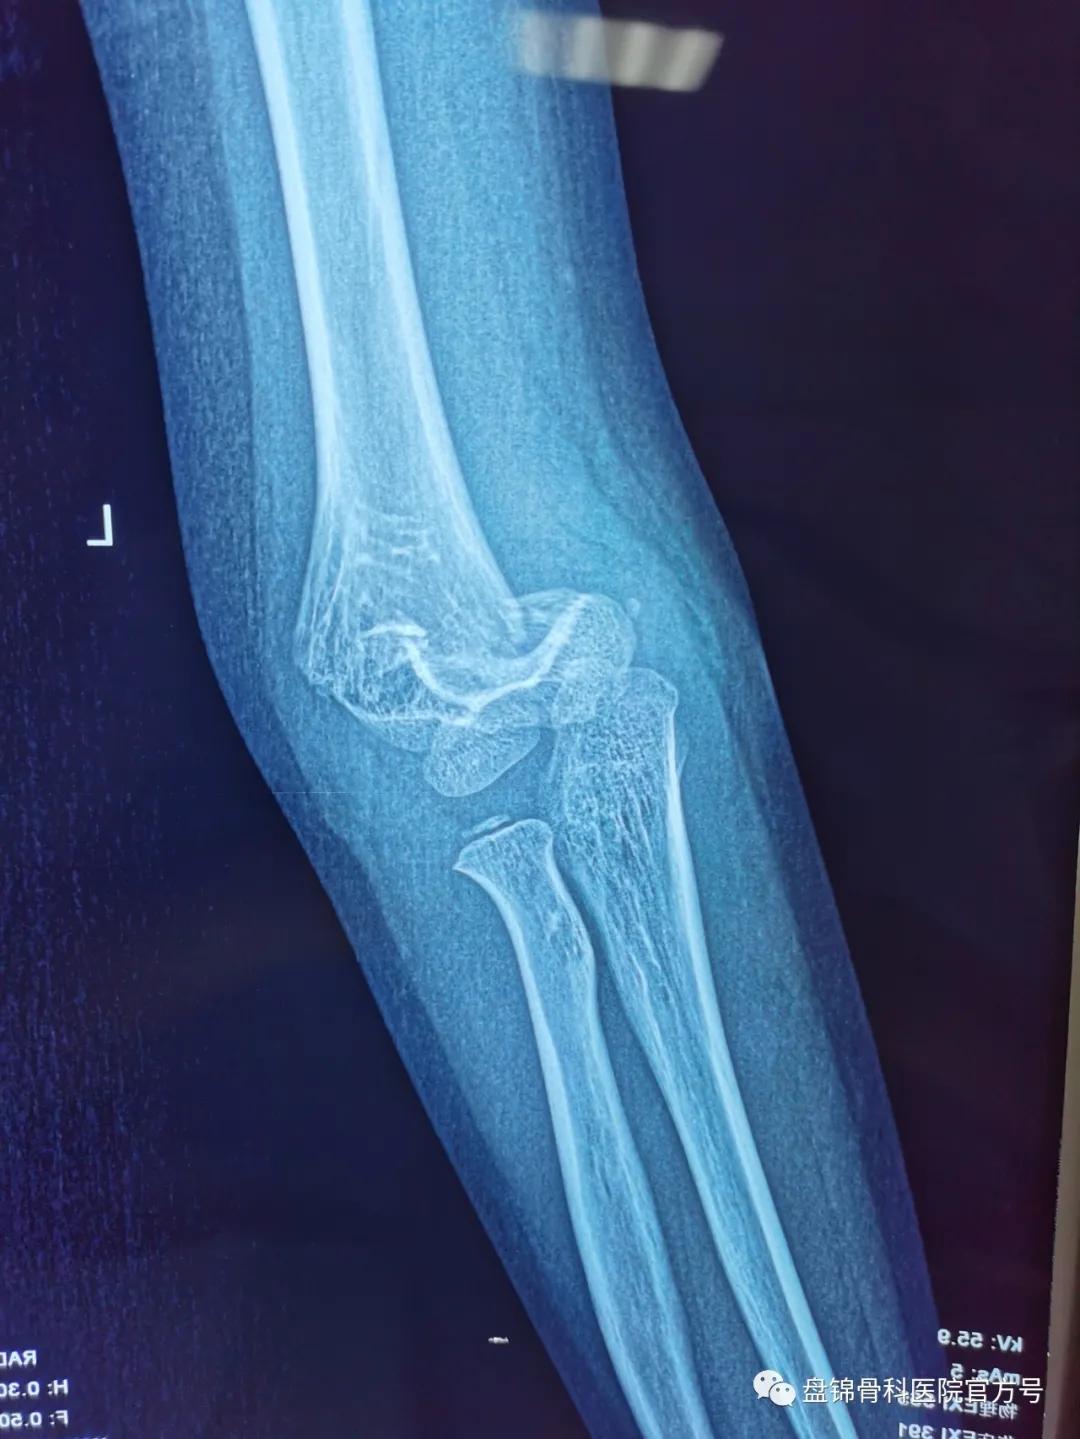

术前DR结果显示“右肱骨髁上骨折”

手足显微外科小儿病区袁钢主任第一时间查看患儿及阅片后跟家属交代, DR结果显示 “右肱骨髁上骨折” ,这种骨折应该手术治疗,可以行 右肱骨髁上骨折闭合复位克氏针内固定术。闭合复位克氏针内固定术可以解决手术切开治疗遗留伤疤,只留下针眼大小的伤疤,可早期活动关节,术后疼痛轻,恢复快。